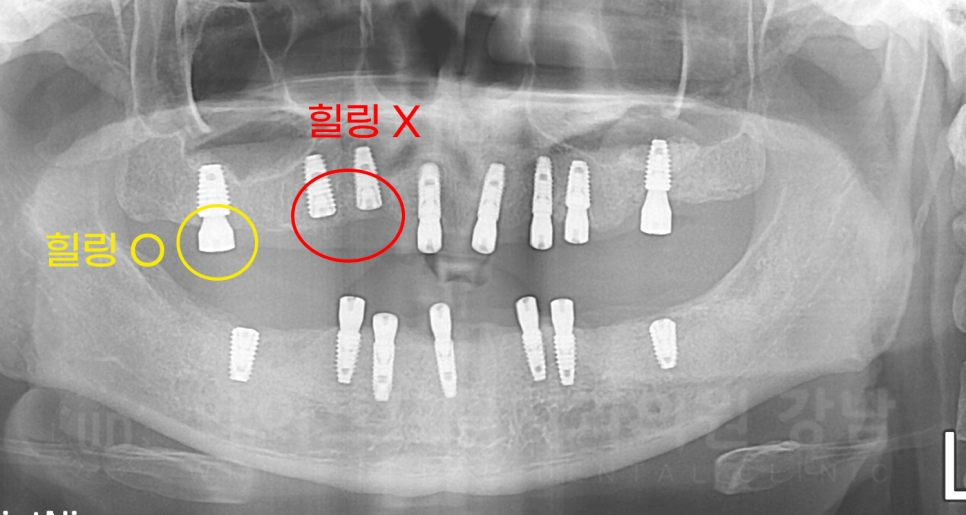

임플란트 2차 수술은 뭔가요?

2차 수술은 잇몸뼈 안에 있는 임플란트를 보철 제작을 위해 겉으로 꺼내는 술식입니다.

1차 수술 후 고정력이 좋은 임플란트는 이렇게 힐링까지 체결하고 잇몸을 봉합합니다.

1차 수술에 비해 굉장히 간단하고, 치료 후에는 구강 내 작은 나사가 달려있습니다.

힐링 어버트먼트라고 하는 부분인데요, 이름 그대로 잇몸의 회복을 도와줍니다.

초기 임플란트 고정력이 좋으면

1차 수술과 2차 수술을 한 번에 진행합니다.

▲ 전악 식립 후 X-RAY입니다.

노란색 동그라미는 1+2차를 동시 진행한 경우이고

빨간색은 2차 수술이 필요한 상태입니다.

환자분도 초기 고정력이 좋은 임플란트는 1+2차를 동시에 진행했고,

유착기간이 필요했던 몇몇 개의 임플란트만 2차 수술을 진행하고 보철 제작에 들어갔습니다.

20.09.05 2차 수술 진행 → 20.10.17 보철 제작 시작